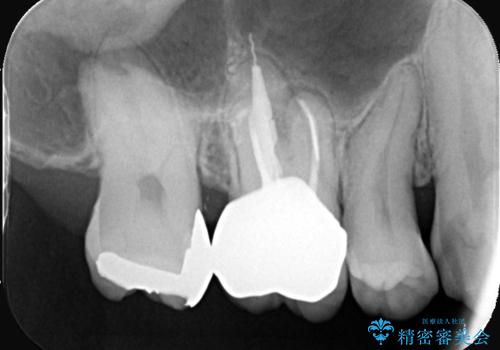

- 主訴:銀歯の入っている歯の側面に穴が空いている気がする。そこに食べ物が詰まる。

右上6番目の歯の被せものと歯質の境目に大きな窪みが出来ており、そこに汚れが停滞しやすい状態で虫歯もそこから広がっていたため、被せもののやり替えと必要に応じて土台の立て直しも行うこととしました。

メタルクラウンを除去したところ近心面に大きな窪みとう蝕を認め、ファイバ-コアからのやり替えとしました。クラウンは審美性の良いセラミッククラウンを選択されました。